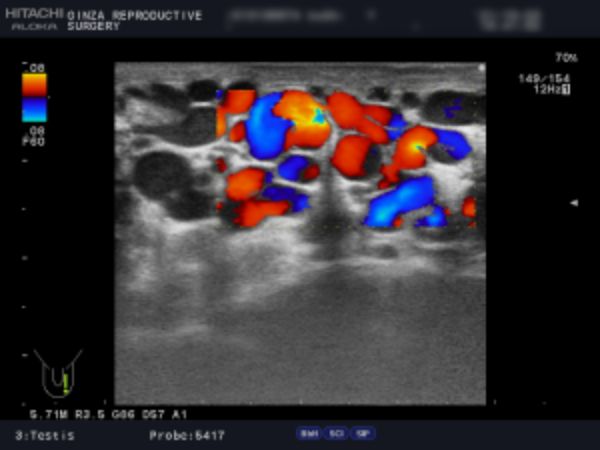

精索静脈瘤の検査は「触診」「エコー検査」によって行います。

精索静脈瘤はその重症度を「グレード」で表します。視診・触診でも度合いを判断することはできますが、正確なことはエコー検査でしか診断することはできません。

軽症の場合、手術の必要はありませんが、当院では診察で「グレード3(見てわかる:陰のうが凸凹している、腫れている)」「グレード2(触ってわかる:腫れている)」、エコー検査で精巣周辺の静脈の太さ3mm以上が複数または2.8mm以上が多数あるものを手術適応としています。

検査は、視診と触診の他、エコー検査で精巣周囲の静脈の太さを確認します。

陰嚢専用の機器を用いてエコー検査を行い、陰嚢の状態を検査します。正確に検査することで的確な手術ができ、再発の可能性を限りなく下げることができます。

エコー検査では、精巣腫瘍、精液瘤、精巣水腫、精巣内石灰化の有無などを確認します。